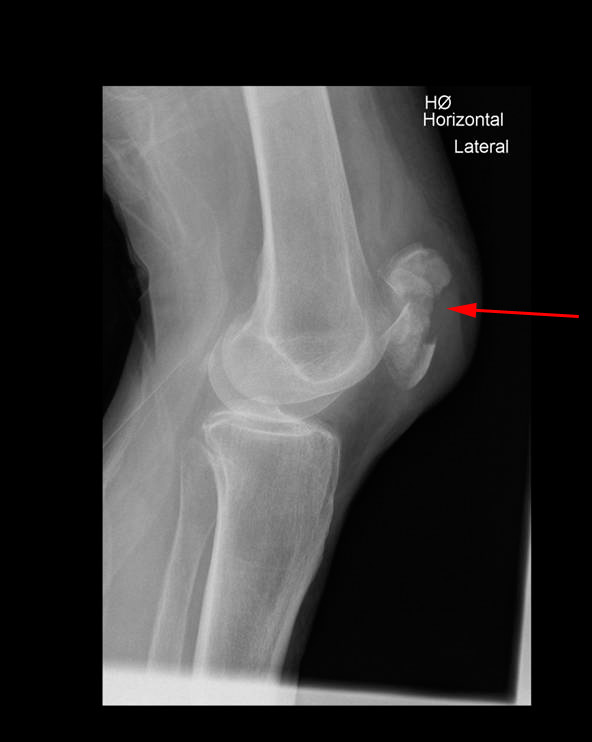

Røntgenbillederne nedenfor viser brud på knæskal set forfra og fra siden:

Brud på knæskal, røntgenbillede

For at se om der er brud, og eventuelt hvor bruddet er, bliver der taget røntgenbilleder af knæet. På billedet skelner man mellem forskudte eller ikke forskudte brud, og mellem længdegående brud, tværgående brud, afrivningsbrud eller knusningsbrud.